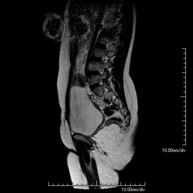

Prova diagnòstica no invasiva que consisteix en l'obtenció d'imatges d'alta definició anatòmica de la pelvis mitjançant l'ús d'un camp electromagnètic i ones de ràdio (amb un emissor i un receptor). No utilitza radiació ionitzant. Es realitza per a l'estudi de patologies d'úter, d'ovari, de trompes i de vagina, ja siguin d'origen tumoral, inflamatori o vascular. També permet valorar les estructures adjacents localitzades a la pelvis i la identificació de les seves alteracions. De vegades és necessari l'ús de contrast intravenós (Gadolini) per caracteritzar les lesions. - RM Pelvis masculina

Prova diagnòstica no invasiva que consisteix en l'obtenció d'imatges d'alta definició anatòmica de la pelvis masculina mitjançant l'ús d'un camp electromagnètic i ones de ràdio (amb un emissor i un receptor). No utilitza radiació ionitzant. No requereix preparació prèvia. En algunes ocasions necessita l'ús de contrast paramagnètic (Gadolini) per caracteritzar les lesions. Aquesta prova permet valorar òrgans com la bufeta urinària, la unió entre els urèters i la bufeta, la pròstata, les vesícules seminals, la uretra i els ossos de la pelvis, entre d'altres. - RM de Fetge